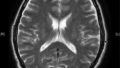

緊急搬送のあと、MRI画像にはやはり大きな影。まずは明後日の朝に開頭手術、その後のことは、怖くて担当医に聞く勇気がありませんでした。